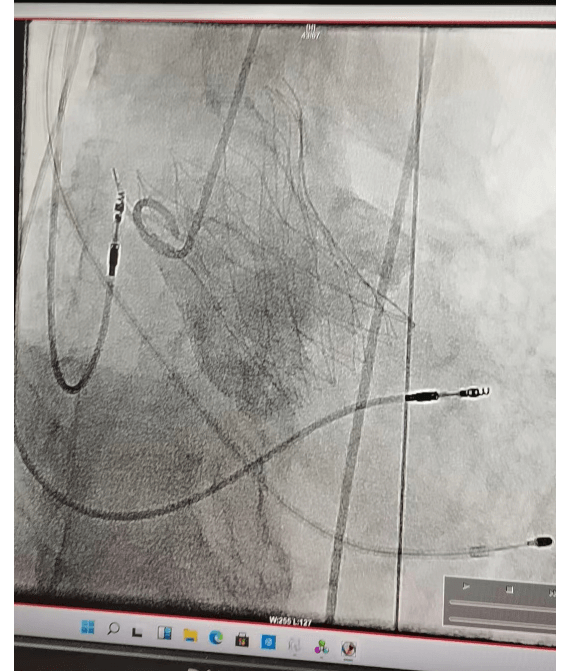

4月11日在全麻下行經(jīng)皮介入下主動脈瓣置換術(shù)。經(jīng)右側(cè)股動脈,在DSA引導(dǎo)下經(jīng)傳輸器將人工主動脈瓣膜送入主動脈瓣環(huán)內(nèi),定位準確后逐步釋放人工瓣膜,完成瓣膜置換,術(shù)后超聲顯示人工瓣膜固定良好,無瓣周漏,無返流。手術(shù)歷經(jīng)約兩小時順利結(jié)束,超聲顯示,主動脈瓣跨瓣壓差基本消失,返流大大減輕。手術(shù)獲得成功,術(shù)后患者24小時下床活動,恢復(fù)良好出院!